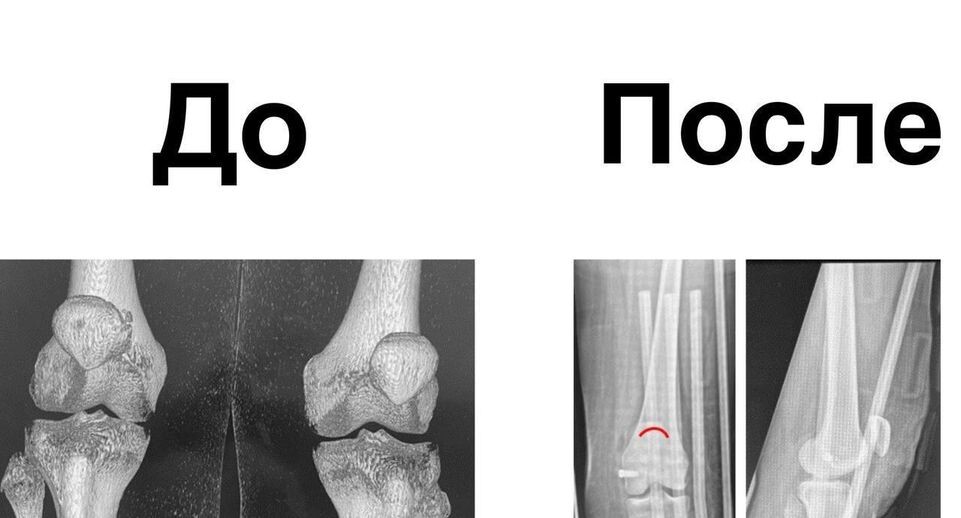

Подростку с хроническим вывихом восстановили подвижность колена в медцентре Рошаля

Врачи Детского клинического центра имени Л. М. Рошаля помогли 15-летней девочке, которая испытывала сильные боли в колене. Она страдала из-за постоянных вывихов коленной чашечки.

Врачи тщательно осмотрели ногу девочки и решили провести хирургическое вмешательство.

«Нам удалось создать новый удерживатель надколенника, который будет препятствовать повторным вывихам коленной чашечки», — рассказал врач Алексей Иванов.